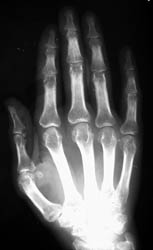

Target areas of the hands primarily involve the interphalangeal joints, especially

at the DIPs. The MCP joints and carpal bones are involved less frequently.

Symmetric well-circumscribed marginal erosions are seen at the involved articular

surfaces. Uncalcified soft tissue nodules and the absence of peri-articular

osteoporosis are additional radiographic features of multicentric reticulohistiocytosis.

Severe progression of the disease can lead to extensive osseous resorption

with foreshortening of the fingers and telescoping digits.